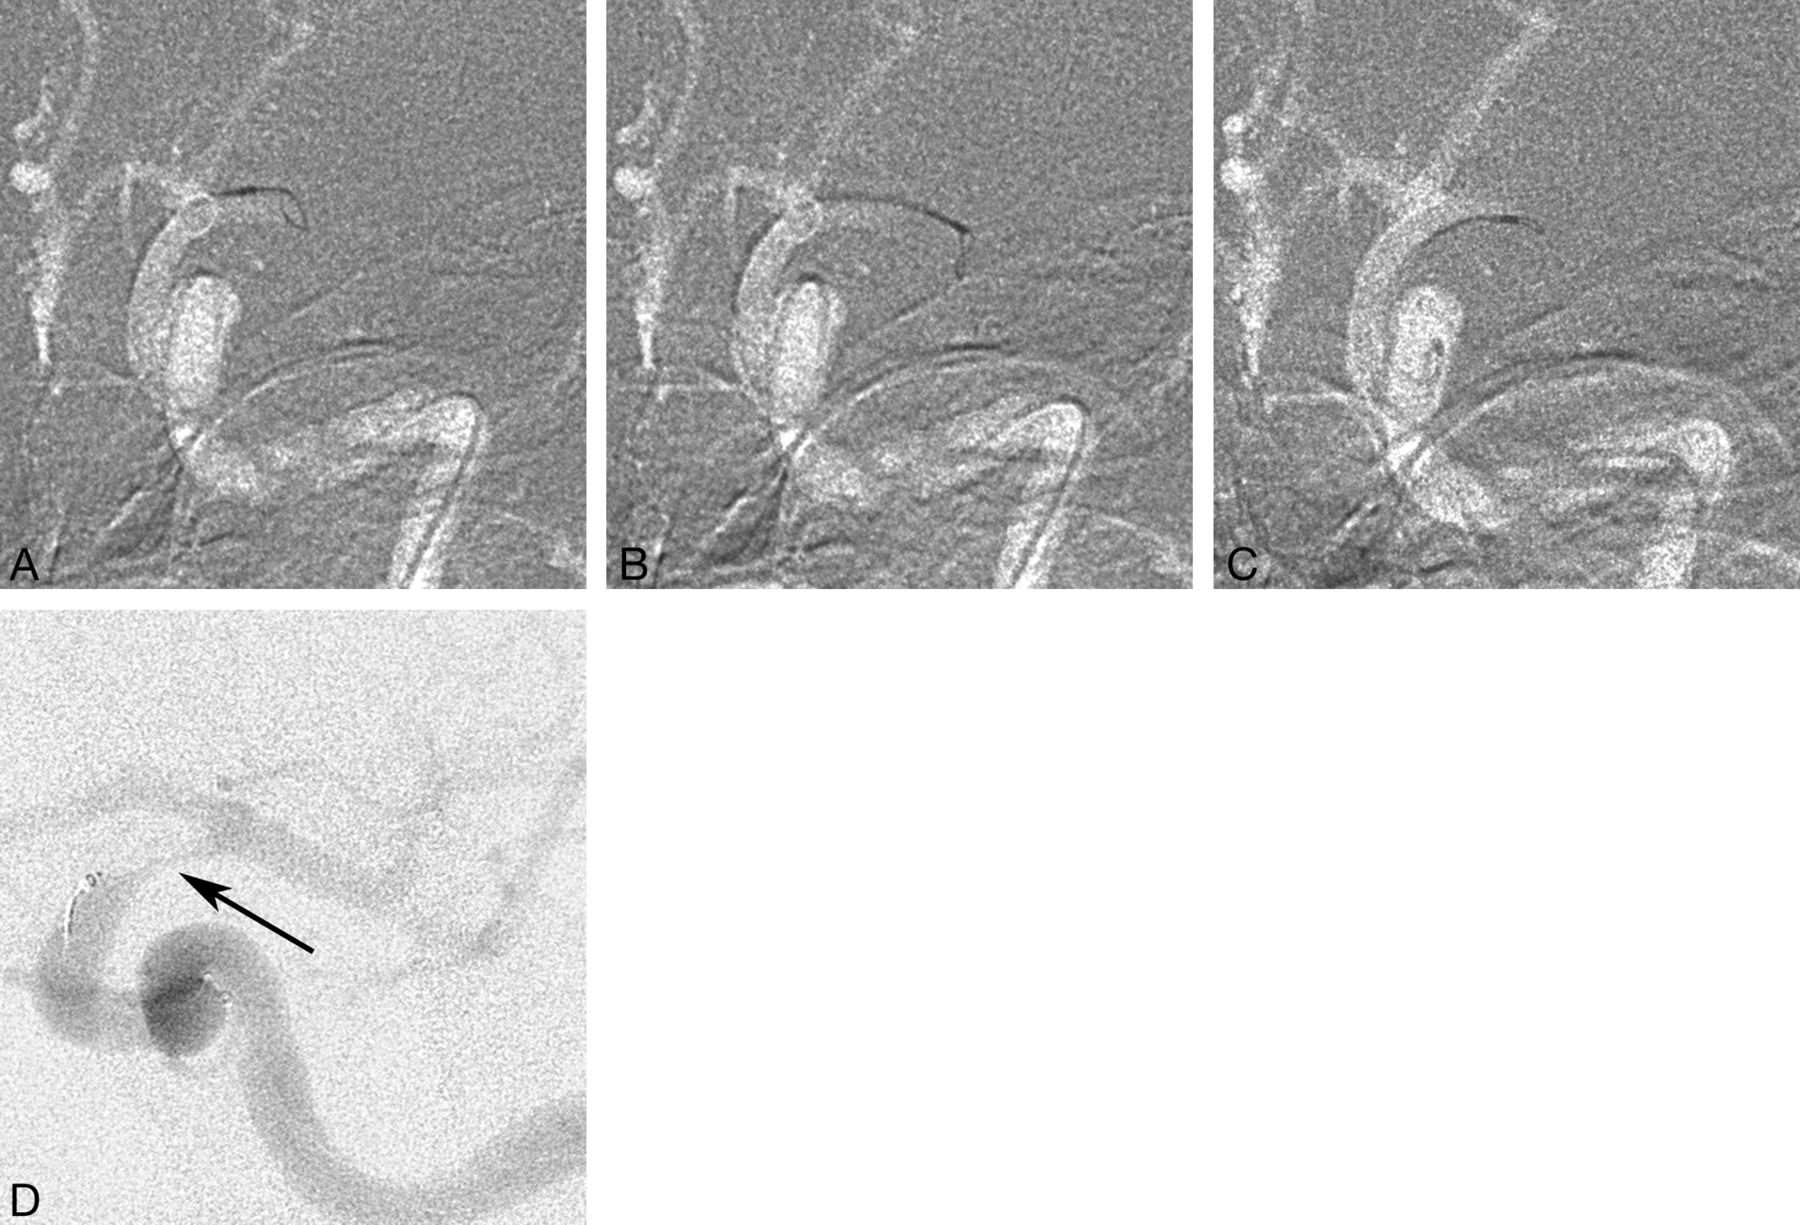

Our study shows that a high recanalization rate can be achieved with the Amplatz GooseNeck snare, which can be used fast and safely for restoration of intracerebral circulation. The Amplatz GooseNeck snare technique was not established among neurointerventionalists in our department from the beginning, and commonly, intra-arterial thrombolysis was used as the first method. When the Amplatz GooseNeck snare became the standard embolectomy method and the stroke logistics were restructured in our hospital leading to an increased proportion of patients receiving intra-arterial treatment, the recanalization rate reached 82% (2006–2011). During this time, a number of new devices were tried in our department, most commonly the Merci retriever first and later the Solitaire FR, the latter being, for the moment, our second device. The Amplatz GooseNeck snare is kept as the device of choice because newer devices have not shown any better results, are more expensive, and have shown a higher complication rate. Moreover, the catheterization time was not longer than in newer devices and may be faster, given that no incubation time is required after deployment and before the retrieval of the device (Fig 1).

A, Occlusion of the left M1 segment with a 4-mm snare pushed out of the microcatheter just enough to open fully and take its built-in shape perpendicular to the catheter and vessel. B, The snare with the microcatheter is pushed forward to engulf the embolus, with a slight deformation of the snare loop indicating that the loop is surrounding the embolus. C, Careful partial withdrawal of the snare into the microcatheter is seen, leaving a small eye outside the catheter tip. D, The microcatheter with the snare is carefully pulled back, and a careful control injection is performed showing the embolus hanging from the catheter tip in the distal ICA (arrow), while the M1 and M2 segments are open (slightly different projection angle than in A–C). The snare and the microcatheter are again pulled back as 1 unit, and aspiration via the guide catheter is performed simultaneously.